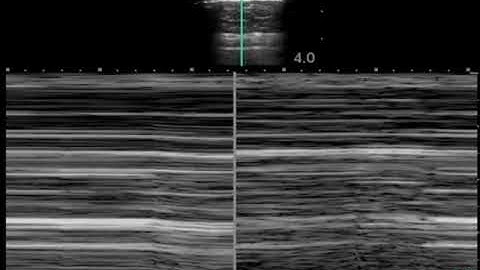

M Mode for Lung Ultrasound - Lung Sliding